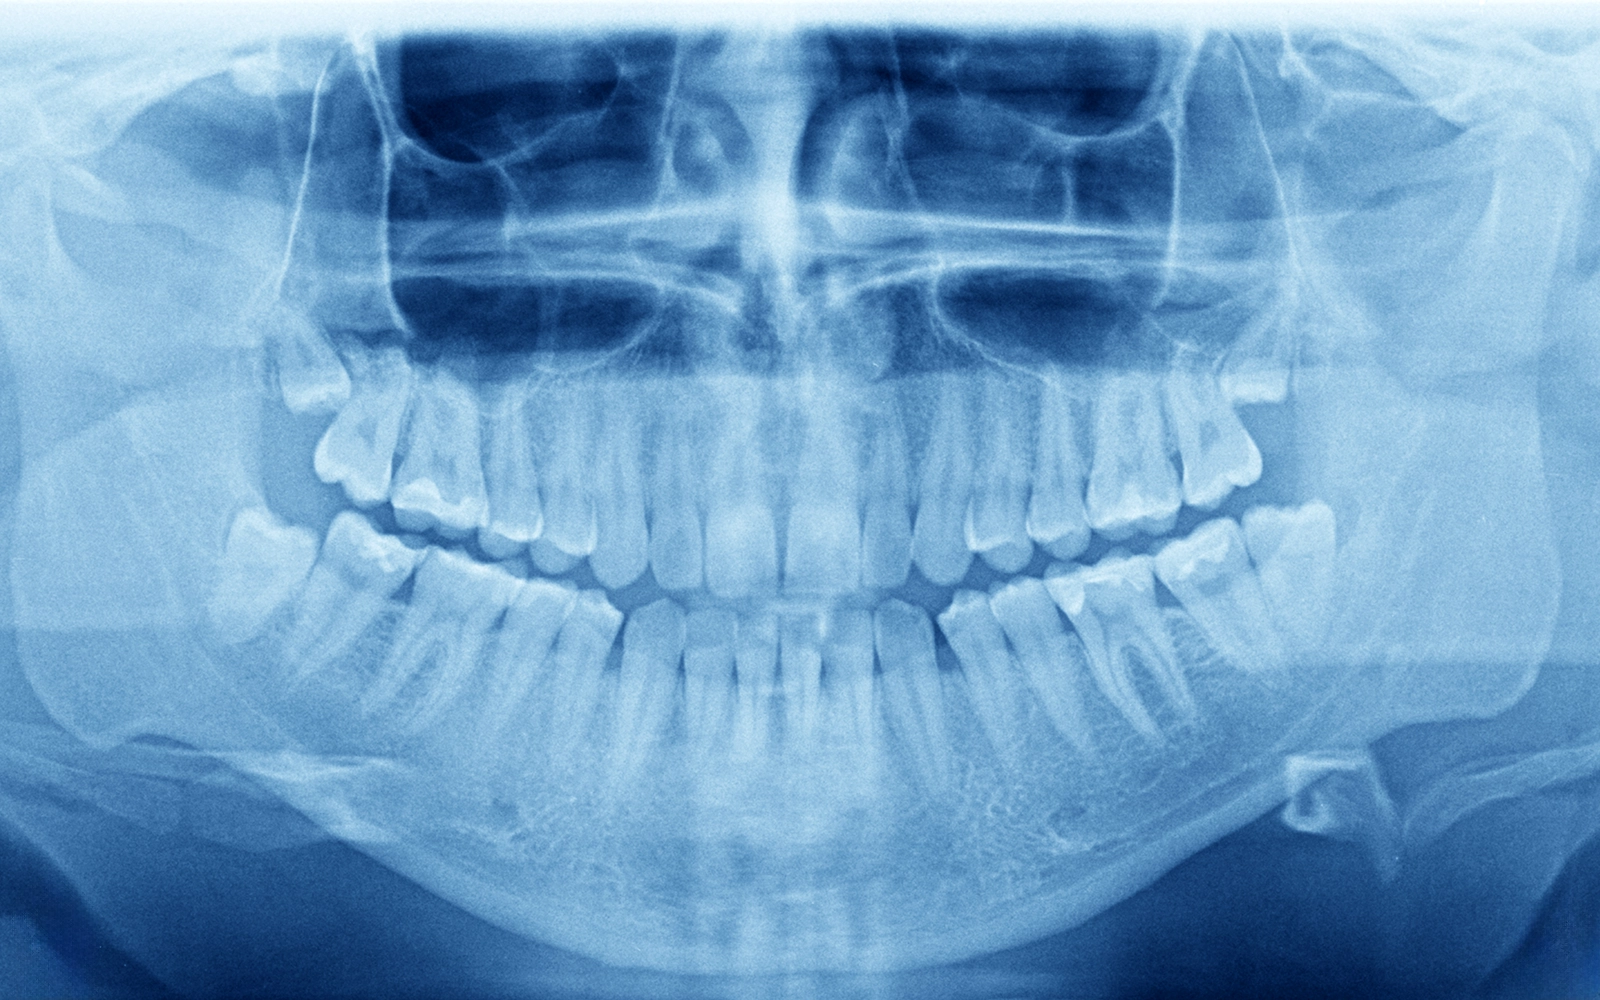

親知らずの抜歯は、口腔外科で最も一般的な処置です。

当院では、大学病院所属の口腔外科専門医が、難症例を含めた親知らずの抜歯に対応しています。埋まっている親知らずや横向きに生えている親知らずでも、院内で安全に抜歯することが可能です。

顎の骨の中にできる嚢胞や腫瘍は、通常は症状がなく、レントゲン検査で偶然発見されることが多いです。

放置すると徐々に大きくなり、骨を破壊してしまうため、発見された場合には早めの治療が推奨されます。